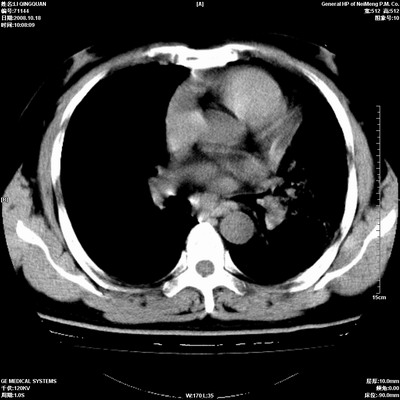

以下是引用duguo在2008-10-19 13:59:00的发言:[br]左肺上叶支气管狭窄,首先考虑中心型肺癌伴阻塞性肺炎\\肺不张.

以下是引用ybing在2008-10-19 12:58:00的发言:[br]左肺上叶阻塞性炎症-建议支气管镜进一步检查除外中央型肺癌

以下是引用随光逐影在2008-10-19 14:31:00的发言:[br]考虑左肺中央型肺癌并左肺上叶阻塞性肺炎,肺不张。